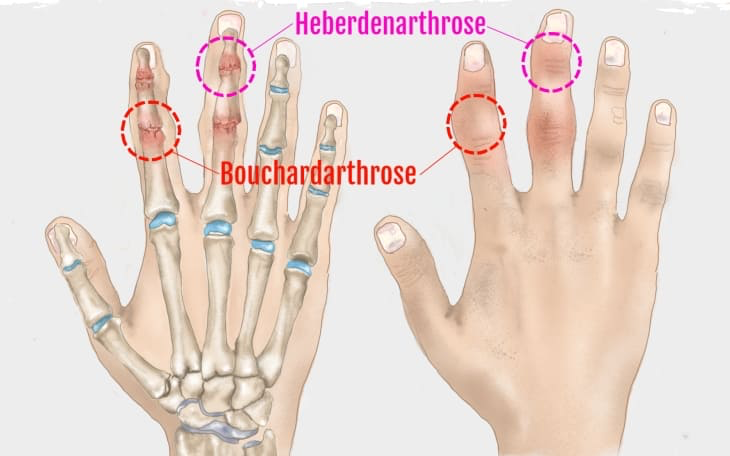

- Gelenkdeformierung (z. B. Heberden-/Bouchard-Knoten an Fingern)

- Hände (DIP = Heberden, PIP = Bouchard)

- Krepitationen, Deformierung (Heberden-/Bouchard-Knoten)

- Typisch: Knie (Gonarthrose), Hüfte (Coxarthrose), Hände (DIP/PIP), WS